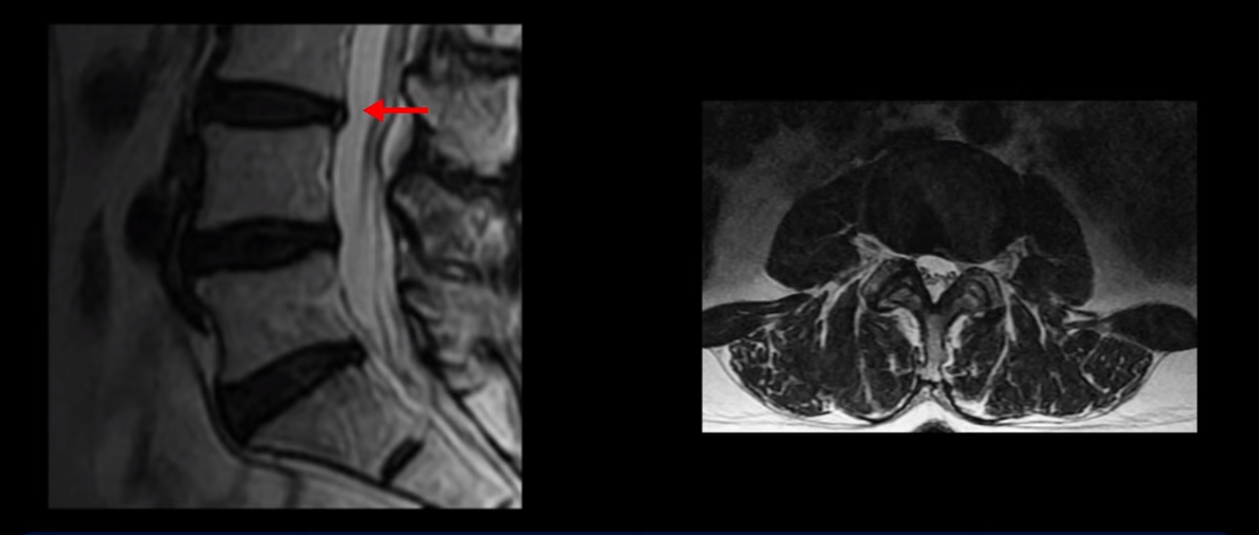

이분 MRI를 보시면 허리 세 마디가 퇴행은 있으나

척추관도 3번 4번

4번 5번

5번 1번

전부 다 충분히 넓고 왼쪽 다리 쪽으로 신경이 나가는 추간공도 전부 다 충분히 넓은 상태입니다.

신경이 눌려 보이지 않는 겁니다. 그러니까 수술 후 MRI를 보고 모든 병원이 전부 다 ‘수술은 잘돼 있다’, ‘아무것도 해줄 게 없다’ 그냥 기다리라고만 얘기했다고 합니다. 신경외과, 정형외과, 재활의학과가 서로 다른 과로 전과시키면서 다들 아무것도 해줄 게 없다고 하니 희망을 잃은 상태였다고 했습니다.